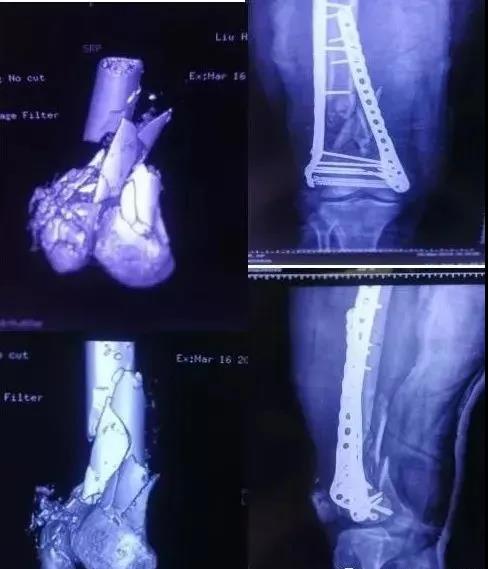

7)胫骨远端(pilon,踝部)

- pilon骨折,高能损伤,6-8h肿胀未形成,可以急诊做,手术时间<3小时。

- 10-14天,分步延期手术策略。

- 踝部骨折手术时机同样取决于皮肤条件。

8)足部骨折(距骨,跟骨,跖骨等)

高能损伤导致的距骨骨折并脱位,建议急诊做。